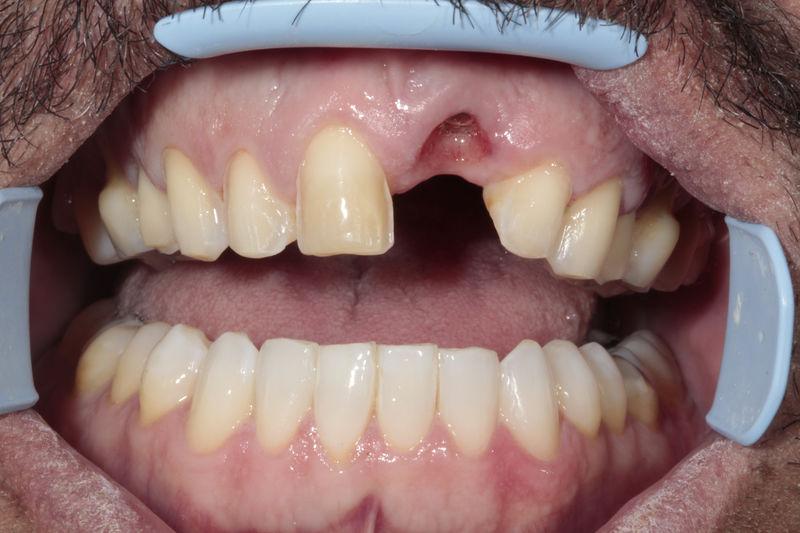

Son estructuras de titanio las cuales se colocan en el hueso y se utilizan para soportar coronas, prótesis fijas, removibles y totales. La colocación de los implantes se hacen previo análisis tomográfico.

Implante fracasado, extracción, carillas, coronas y prótesis fija.